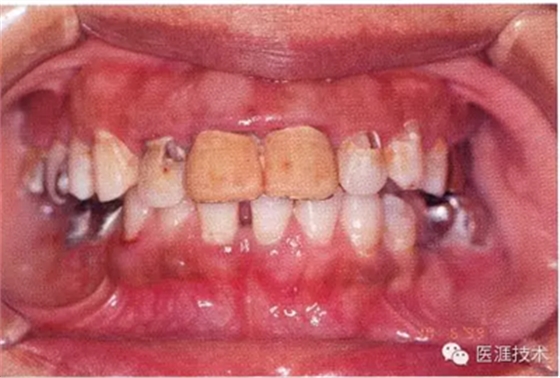

14歲男性牙齦炎的臨床圖像